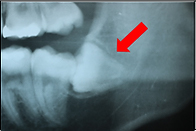

下の写真は、親知らずが横向きに生えていて隙間があります。

下の写真は、その隙間に食べかすが入ってしまっています。

この隙間は下の方が深歯ブラシが届かず、このままでは親知らずと手前の歯が2本とも虫歯になってしまうので抜いたほうが良いケースです。